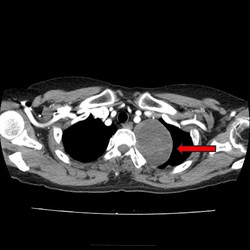

🧬 흉선암이란?

흉선은 가슴 중앙, 심장 위쪽 흉골 뒤에 있는 작은 면역 관련 기관입니다. 성장하면서 기능이 줄어들지만, 성인에서도 호르몬과 면역 세포 교육 역할을 담당합니다.

흉선에서 생기는 암은 크게 두 가지 형태로 나뉩니다:

- 흉선종(thymoma) — 상대적으로 성장 속도가 느리고 예후가 좋은 편

- 흉선암(thymic carcinoma) — 더 공격적이고 전이 가능성이 높은 형태